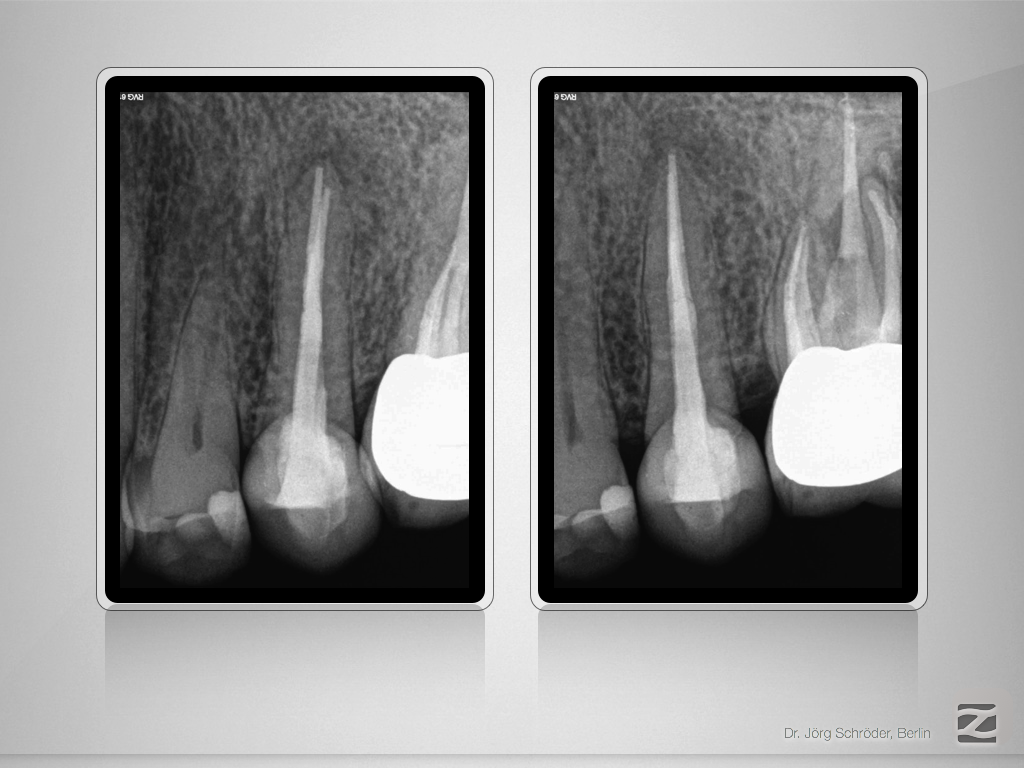

2526d-011

Enter Sandman